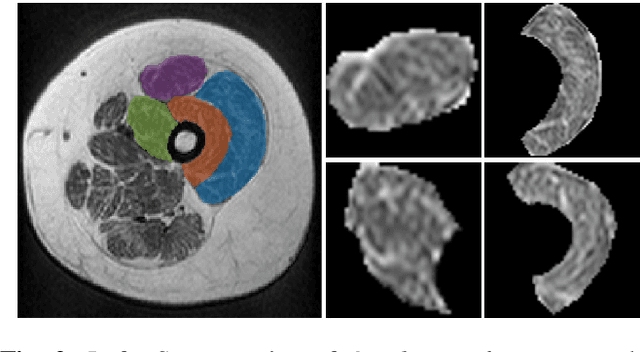

Magnetic Resonance Imaging (MRI) is a non-invasive tool for the clinical assessment of low-prevalence neuromuscular disorders. Automated diagnosis methods might reduce the need for biopsies and provide valuable information on disease follow-up. In this paper, three methods are proposed to classify target muscles in Collagen VI-related myopathy cases, based on their degree of involvement, notably a Convolutional Neural Network, a Fully Connected Network to classify texture features, and a hybrid method combining the two feature sets. The proposed methods was evaluated on axial T1-weighted Turbo Spin-Echo MRI from 26 subjects, including Ullrich Congenital Muscular Dystrophy or Bethlem Myopathy patients at different evolution stages. The best results were obtained with the hybrid model, resulting in a global accuracy of 93.8\%, and F-scores of 0.99, 0.82, and 0.95, for healthy, mild and moderate/severe cases, respectively.